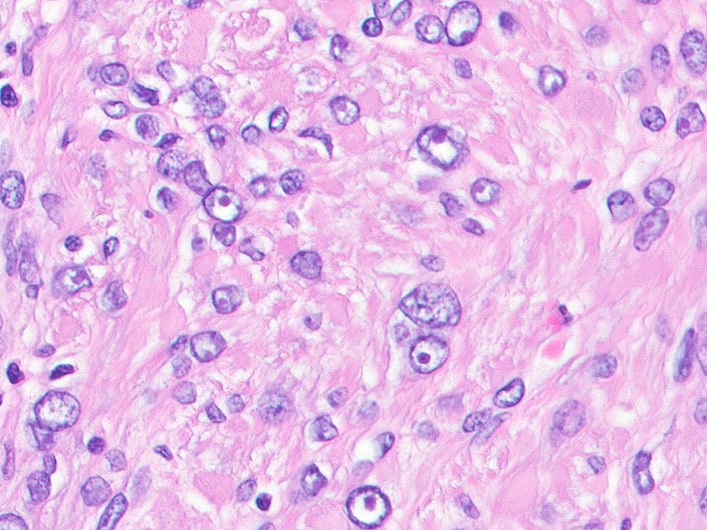

- Rare, benign appearing smooth muscle tumor in lung; may represent hematogenous spread of a uterine leiomyoma or a metastasis of a well differentiated leiomyosarcoma of low malignant potential (Mod Pathol 2006;19:130)

- Usually women 36 - 64 years, mean 44 years, with history of uterine leiomyoma

- Lung is most common site, sparing bronchus and pleura; also reported in lymph nodes, retroperitoneum, skin, bone, spine, skull base, heart

- Usually multiple nodules, up to a few centimeters in size

- Lesions tend to regress during pregnancy or after oophorectomy and stabilize or grow slowly in postmenopausal women

- Usually asymptomatic but may present with dyspnea, cough, hemoptysis, chest pain

- Chest Xray: diffuse, bilateral nodular opacities; rarely associated with miliary pattern, cavitary lesions, multiloculated cysts, interstitial lung disease (J Thorac Dis 2014;6:E92)

- Surveillance acceptable treatment for indolent, asymptomatic disease

- 32 year old woman with pulmonary benign metastasizing leiomyoma (J Thorac Dis 2014;6:E92)

- 52 and 56 year old women with benign metastasizing leiomyoma (Case Rep Oncol Med 2014;2014:842801)

Microscopic (histologic) images

Contributed by Sabrina Croce, M.D., Ph.D., Kristina Doytcheva, M.D., Jennifer A. Bennett, M.D. (Case #508) and @Andrew_Fltv on Twitter